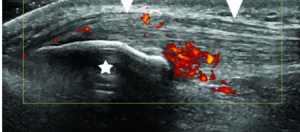

or like this….

with plenty more examples of it, illustrating how awesome it is and why we should use bedside ultrasound to evaluate tendons more.